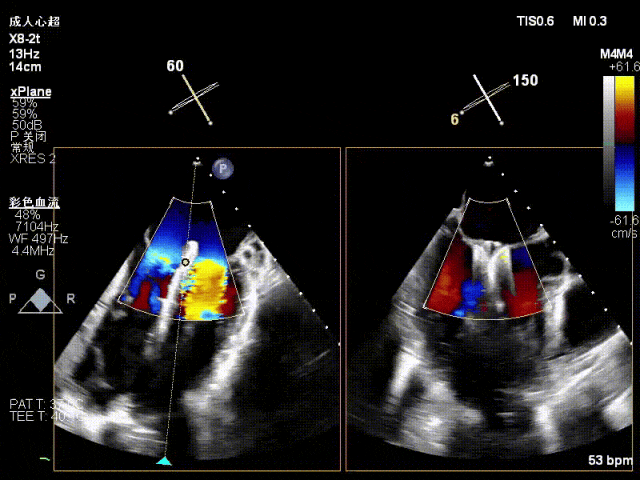

术中超声(关键步骤)

术中超声要点